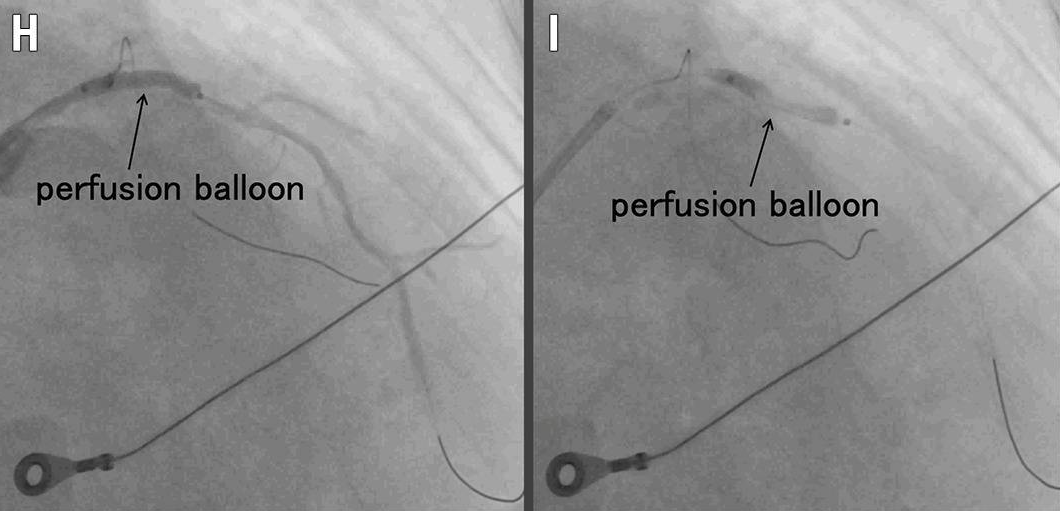

H. 灌注球囊封堵入口:LAD血流恢复

I. 灌注球囊远端开窗:建立真-假腔交通

a. 入口封堵:

使用 3.0/20mm 灌注球囊(Ryusei [Kaneka Medix])在疑似夹层入口处进行短时间扩张。在LAD灌注得以恢复的情况下,能够对LAD进行造影(图 1H)。

b. 远端开窗:

在疑似夹层远端处,也以额定压力扩张灌注球囊以建立真-假腔交通,实现开窗(图 1I)。IVUS显示真腔扩大,真腔与假腔之间有多个连通,随后胸痛和 ST 段抬高缓解(图 1J、视频4)。冠状动脉造影显示LAD血管腔扩大,血流恢复至 TIMI 3 级。